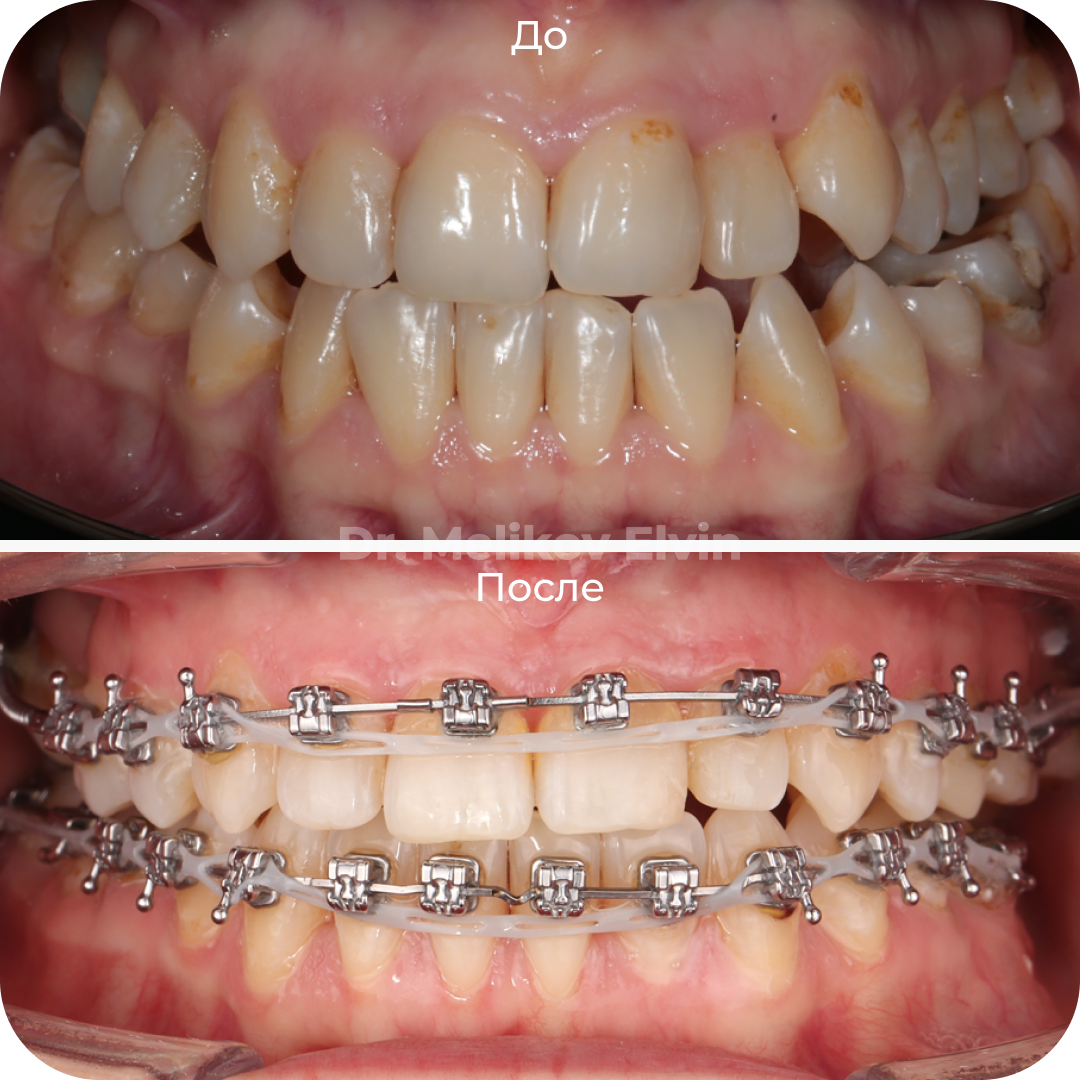

На этапе ортодонтического лечения:

До и после лечения